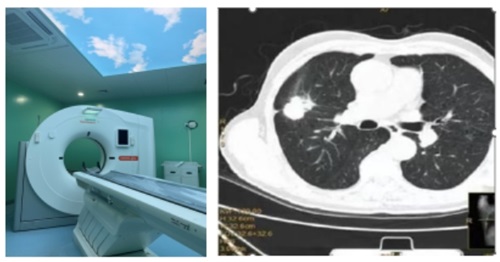

如何進(jìn)行肺癌篩查?

肺癌篩查很簡(jiǎn)單,但并不是所有的人都需要進(jìn)行肺癌篩查,指南建議50-74歲的人群為重點(diǎn)篩查人群。對(duì)于75歲及以上的老年人可以考慮機(jī)會(huì)性篩查。需要結(jié)合年齡、是否吸煙和是否有高危因素來(lái)判定是否是肺癌高危人群和具備肺癌危險(xiǎn)因素,如果具備,就需要去醫(yī)療機(jī)構(gòu)去進(jìn)行低劑量螺旋CT檢查。

微信截圖_20240419181452.png

拿到CT報(bào)告單,如果看到鈣化結(jié)節(jié)、纖維條索,大家不用太擔(dān)心,多數(shù)是既往肺部病灶遺留的陳舊性病變或瘢痕。篩查或體檢發(fā)現(xiàn)的肺部結(jié)節(jié)絕大多數(shù)是良性結(jié)節(jié),大家不必看到結(jié)節(jié)就恐慌。如果結(jié)節(jié)大小6mm以下,可以不用太擔(dān)心。如果結(jié)節(jié)大小6mm以上,建議到醫(yī)院呼吸??苹蛐赝饪凭驮\,聽從醫(yī)生的專業(yè)建議。